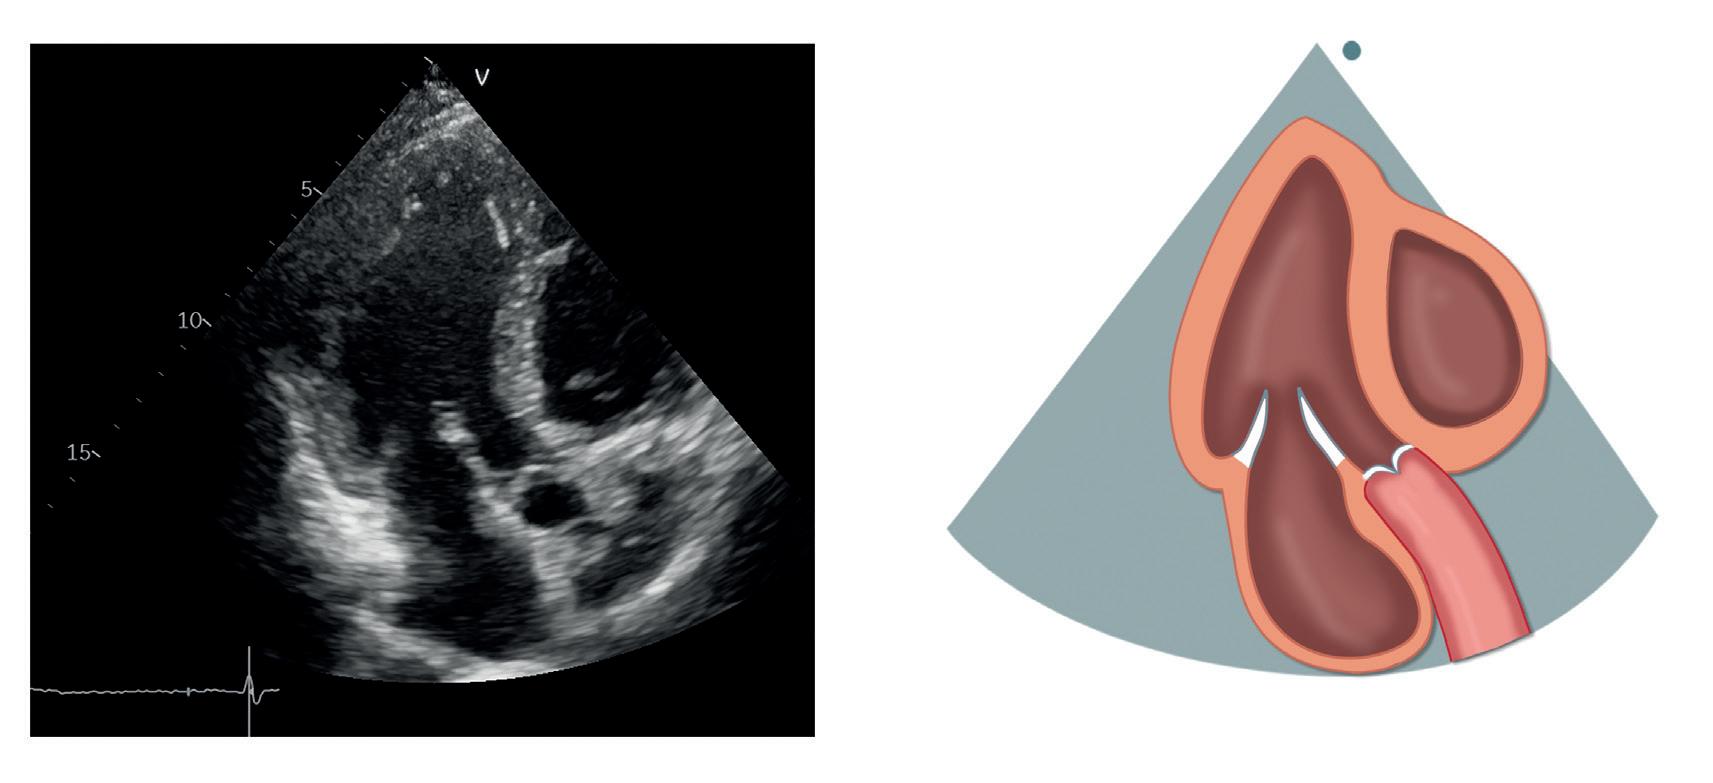

Parasternal langakseprojeksjon

I denne projeksjonen ses hjertet i langakse fra venstre (figur 2.2).

Subkostal Høyre parasternal Figur 2.1: De ulike projeksjonene og plasseringen av transduseren ved TTE Mitralkla en (MK) Venstre atrium (VA) Venstre ventrikkel (VV) LVOT Aortakla en (AK) Ventrikkelseptum (IVS) Høyre ventrikkel (HV) IVS HV LVOT VV MK VA AK Figur 2.2: Parasternal langakseprojeksjon

Øverst i bildet, anteriort mot transduseren, ligger høyre ventrikkels utløpstraktus (RVOT). Posteriort for den ligger venstre ventrikkel med anteriore septum og inferolaterale (også kalt posteriore) vegg. Ventrikkelens lengdeakse skal ligge horisontalt i bildet, og apex skal som regel ikke være synlig, ellers har vi vinklet transduseren feil. Videre ses venstre atrium nede til høyre i bildet, og hos noen kan aorta descendens i kortakse visualiseres posteriort for atriet. Sinus coronarius kan ses i bakkant av atriet nede ved atrioventrikulærovergangen, men er knapt synlig med mindre den er dilatert.

Venstre ventrikkels utløpstraktus (LVOT) og aortaklaffen skiller venstre ventrikkel og aorta ascendens. To av klaffens tre kusper er synlige: Anteriort ligger den høyre koronare kuspen, mens den posteriore vanligvis er den non-koronare kuspen – men man er så nær kommissuren mot den venstre koronare kuspen at man unntaksvis kan visualisere eller gjennomskjære denne. Aortaroten med sinus Valsalvae, den sinotubulære overgangen og proksimale aorta ascendens ligger til høyre i bildet. Et tips for å visualisere mer av aorta ascendens er å flytte transduseren ett interkostalrom høyere opp. Fra denne posisjonen kan også LVOT og aortaroten ofte komme bedre frem.

Posteriort for aortaklaffen ligger mitralklaffen med sitt fremre og bakre seil. Begge er festet til papillemusklene via chordae tendineae. Perikard ses som en høyekkogen struktur som omgir hjertet.

Tabell 2.1 lister opp sentrale målinger i parasternal langakseprojeksjon

Tabell 2.1: Sentrale målinger i parasternal langakseprojeksjon

Målinger i parasternal langakseprojeksjon

Veggtykkelser (endediastolisk) og dimensjoner (endesystolisk, endediastolisk) av venstre ventrikkel

Proksimale RVOT (endediastolisk)

Aortaannulus’ diameter (midtsystolisk)

Sinus Valsalvae, den sinotubulære overgangen og aorta ascendens (endediastolisk)

Mitralannulus og lengden av mitralseilene